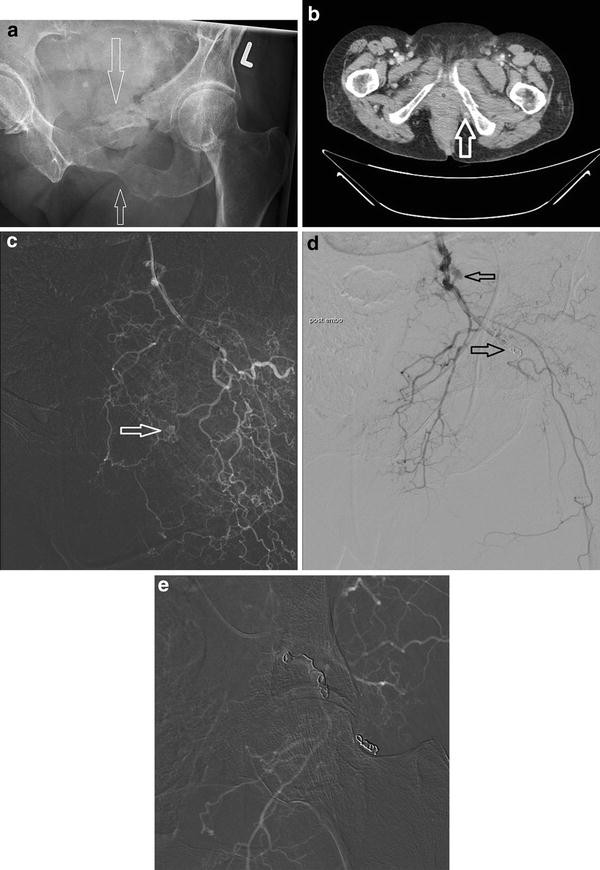

A D This Patient Was Admitted In Shock After Blunt Abdominal Trauma A Download Scientific Diagram

Importance Of Both Internal And External Iliac Artery Interrogation In Pelvic Trauma As Evidenced By Hemorrhage From Bilateral Corona Mortis With Unilateral Aberrant Origin Off The External Iliac Artery

www.hindawi.com